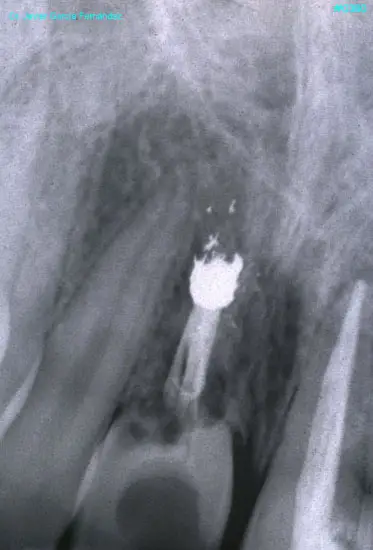

ATLAS DE CIRUGIA PERIODONTAL